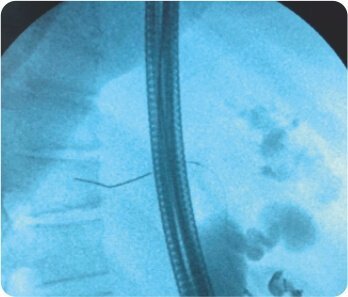

CBD এর EUS নির্দেশিত পাংচার ডুডেনামের প্রথম অংশ থেকে করা হয়েছিল। কোল্যাঞ্জিওগ্রামের পরে, ট্র্যাক্টটি সিস্টোটোম দিয়ে ক্রমান্বয়ে 10 ফারেনহাইট পর্যন্ত প্রসারিত করা হয়েছিল এবং একটি 60x10 মিমি সম্পূর্ণ আচ্ছাদিত বিলিয়ারি স্টেন্ট স্থাপন করা হয়েছিল যা D1 এবং CBD এর সাথে সংযোগ স্থাপন করে। একটি 7F 7cm ডবল পিগটেল প্লাস্টিক বিলিয়ারি স্টেন্ট মেটাল স্টেন্টের মধ্যে স্থাপন করা হয়েছিল যাতে এর স্থানচ্যুতি রোধ করা হয়। কোন পেরিপ্রোসিডারাল জটিলতা ছিল না। এক সপ্তাহের মধ্যে তার বিলিরুবিন স্বাভাবিক হয়ে যায় এবং তাকে কেমোথেরাপি করা হয়।

choledochoduodenostomy with a FCSSEMS (সম্পূর্ণভাবে আচ্ছাদিত স্ব-প্রসারিত ধাতব স্টেন্ট)